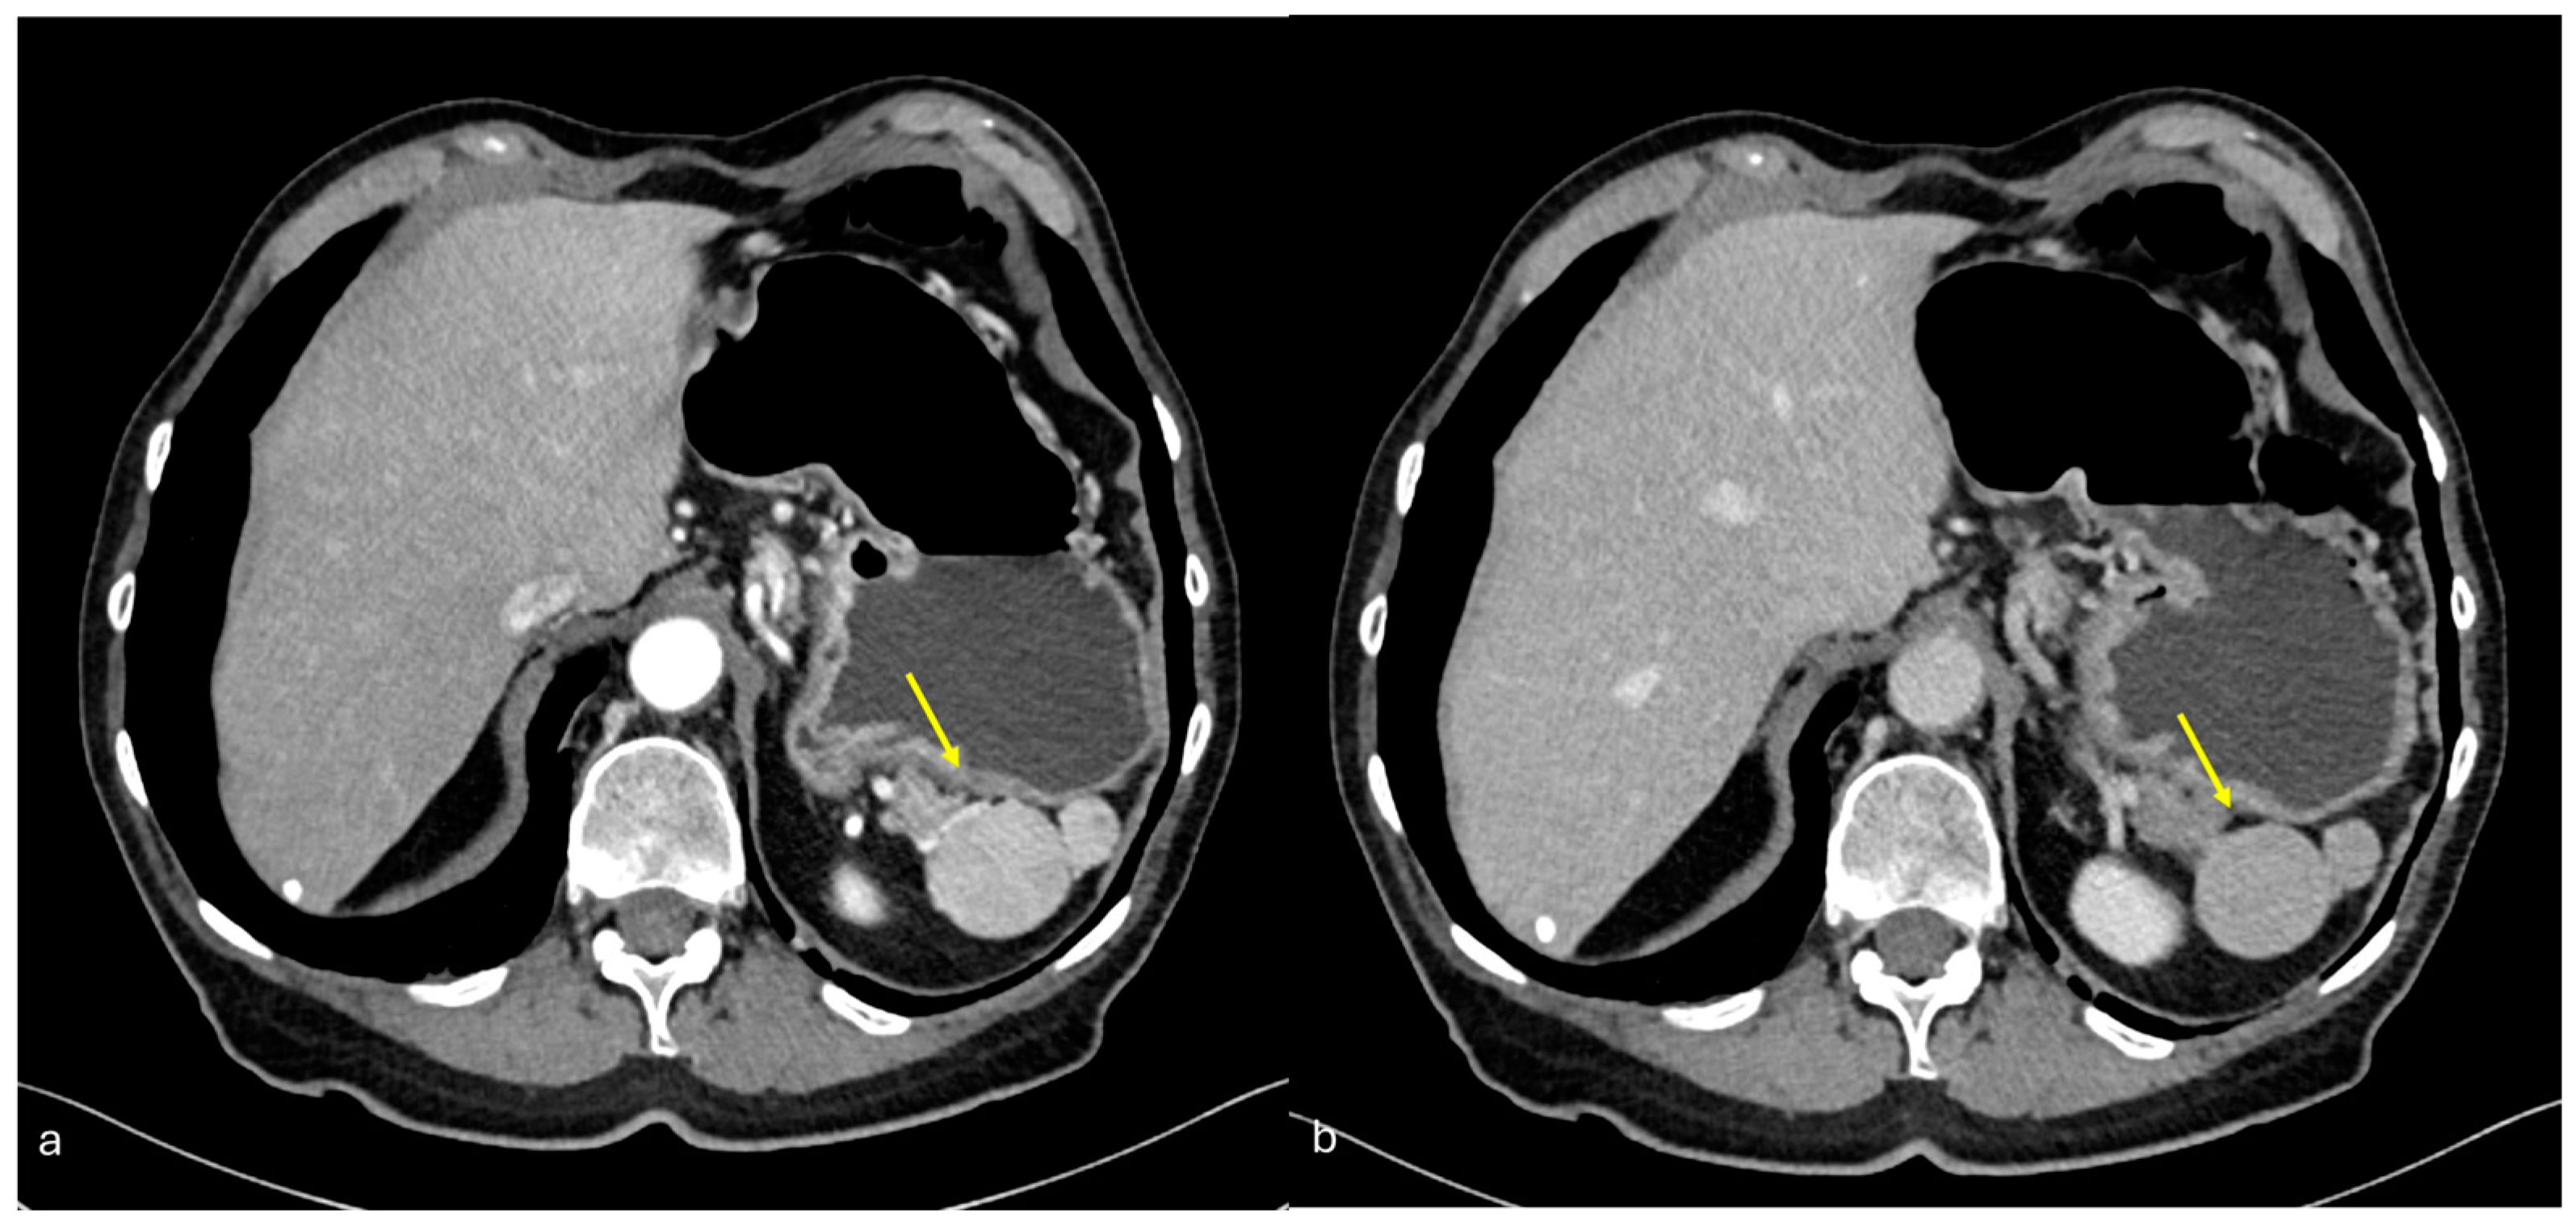

- Plaque pattern: confluent nodular plaques, typically involving the lower surface of the right diaphragm (Figure 3);